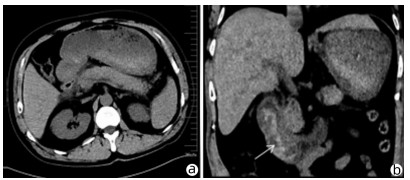

Solitary fibrous tumor of the liver: A case report

Xuecheng LI, Ying FAN, Shuodong WU

2022, 38(3): 632-633. DOI: 10.3969/j.issn.1001-5256.2022.03.026

Abstract(917) HTML (232) PDF (2657KB)(72)

Abstract: